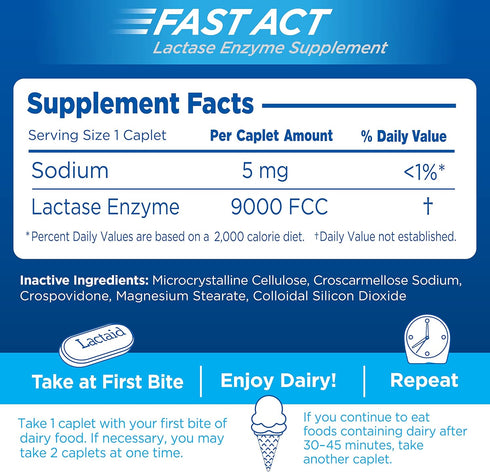

Formulated with 9000 FCC lactase units of natural lactase enzymes, the caplets break down milk sugar to reduce discomfort from dairy sensitivity due to lactose

The easy-to-swallow dairy digestive aid is certified Kosher and is suitable for both adults and children, ages 4 and up

The fast-acting formula of the lactase pills starts working with your first bite or sip of dairy; if you continue to eat foods containing dairy after 30-45 minutes, take another caplet for continued relief